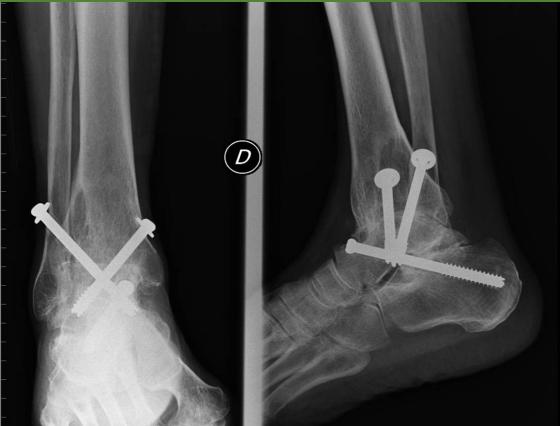

Surgical Considerations

- Timing: When conservative measures fail

- Options:

- Arthroscopy (selective cases)

- Osteotomy (young patients with unicompartmental disease)

- Total knee arthroplasty (end-stage disease)